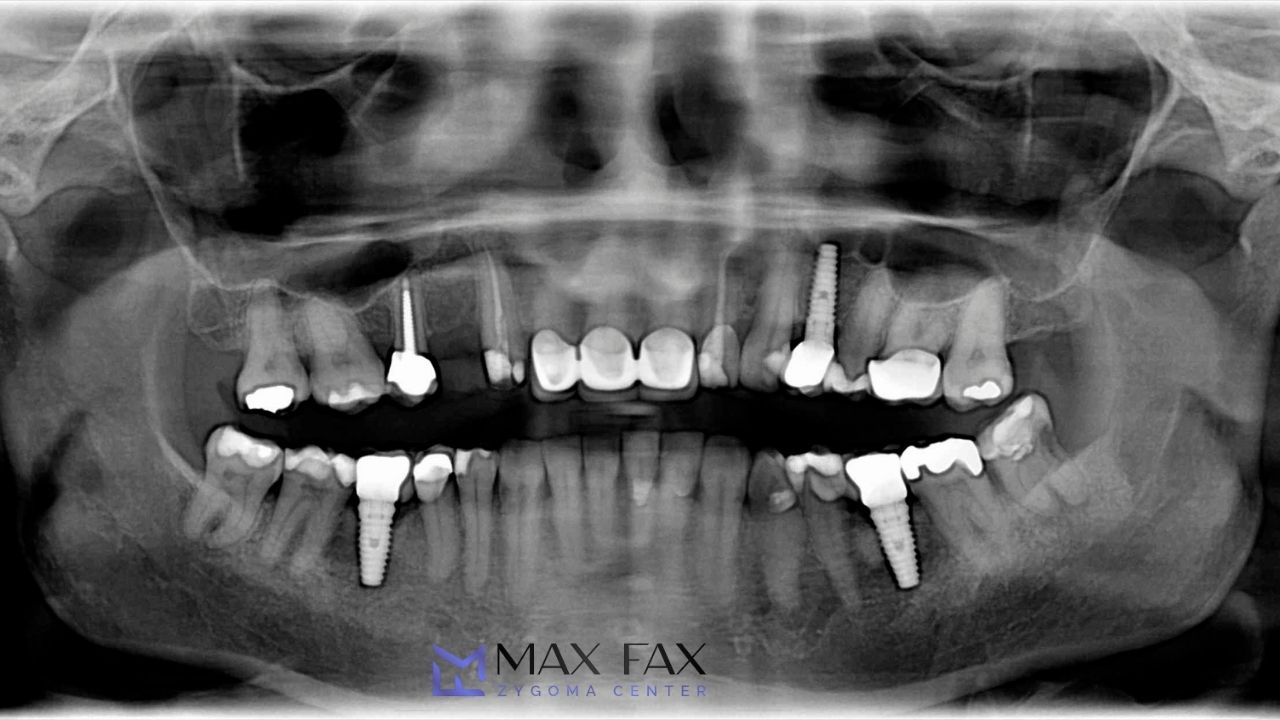

Evaluating Bone Density Before Surgery

Before placing zygomatic dental implants, surgeons use advanced imaging such as 3D CBCT scans. These scans reveal bone density levels, sinus anatomy, nerve position, and cheekbone structure. This precise evaluation ensures that implants are placed safely and accurately.